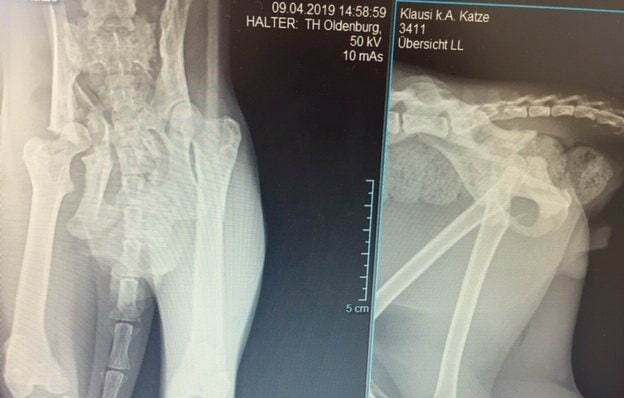

Klausi hat eine gebrochene Hüfte

Bei Kater Klausi fiel auf, dass er etwas wackelig läuft. Beim Röntgen kam nun heraus, dass er einen alten Hüftbruch hat, der allerdings schon von alleine eher unschön zusammengewachsen ist. Klausi muss nun Muskeln aufbauen und kann hoffentlich bald wieder unbeschwert durch die Gegend springen.